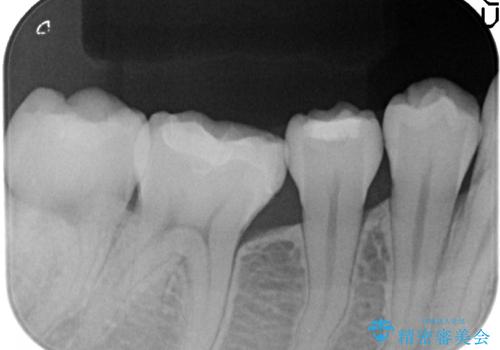

銀歯及び虫歯を除去後、セラミックインレーによる修復を行いました。

当院のセラミックインレーはemaxという強度と審美性に優れた材料を使用しています。

またプレス方式でインレーを製作しているため、削り出しで製作するCADCAMより優れた適合性も持ち合わせており、虫歯が再発しにくい修復物です。